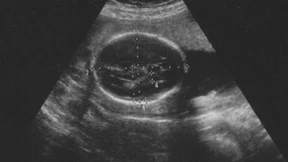

Ein Junge oder ein Mädchen, und ist es gesund? Was wollen Schwangere vor der Geburt über das Ungeborene wissen? Grete Götze hat Ärzte, werdende und gewordene Eltern gefragt.